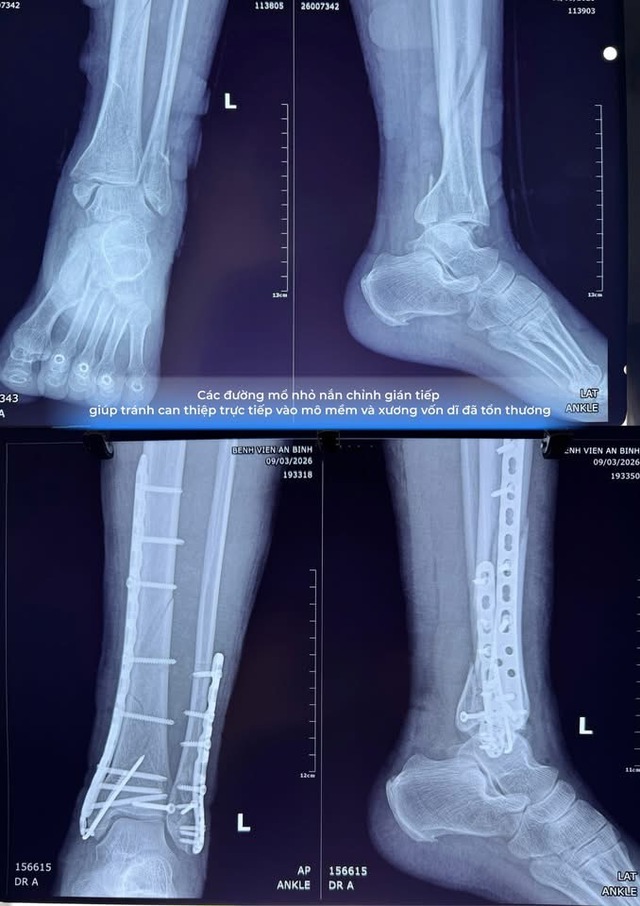

Khi nền mô mềm đã ổn định, các bác sĩ quyết định áp dụng kỹ thuật kết hợp xương xâm lấn tối thiểu (MIPO) thay vì mổ hở truyền thống.

Theo BSCKII Phạm Văn Nhật, phương pháp mổ hở thường đòi hỏi những đường rạch da dài và bóc tách mô rộng để bộc lộ xương gãy. Trong trường hợp nền da đã từng bị viêm mô tế bào, cách tiếp cận này có thể dẫn đến hoại tử da sau mổ.

Với kỹ thuật xâm lấn tối thiểu, các bác sĩ chỉ cần những đường rạch da nhỏ khoảng 1–2 cm để đưa nẹp và vít vào cố định xương, giúp giảm thiểu tối đa tổn thương mô mềm.

Trước hết, quá trình nắn chỉnh xương được thực hiện dưới sự hỗ trợ của hệ thống C-Arm, cho phép chụp X-quang thời gian thực ngay trong phòng mổ. Nhờ đó, các bác sĩ có thể đưa các mảnh xương về đúng vị trí giải phẫu với độ chính xác cao mà không cần mở rộng vết mổ.